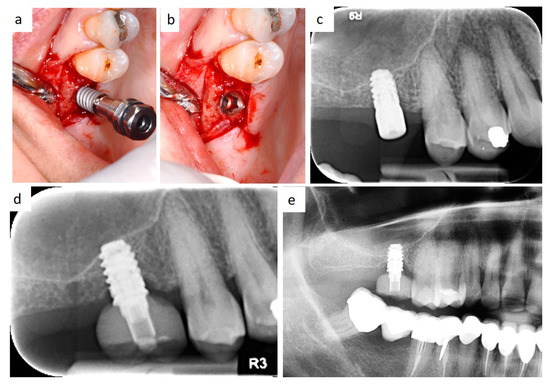

Bone loss around implant was measured at the time of second surgery (three months later) with healing cup positioning (values ranging from 0 to 0.6 mm; median value: 0.1 mm) and also after two years (values ranging from 0.4 to 1.3 mm; median value: 0.7 mm). Clinical post-operative complications did not occur. (Figure 6a–e and Figure 7a,b) To date, no implant failure has occurred during the ten-year follow-up, as summarized in Table 1.

Figure 6. Intraoperative view of implant insertion by muco-periosteal flap elevation (a,b); the implant diameter is larger than implant site preparation, thus promoting bone dislocation in the apical direction by the self-tapping capability of the fixture and high primary stability. Radiological follow-up 3 months after insertion (c), 2 years after prosthetic rehabilitation (d), and after 10 years (e).